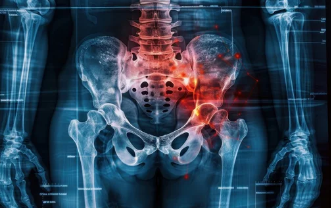

4. 수술적 치료: 척추 전방전위증의 심각한 경우

척추 전방전위증이 진행하여 일상생활이 어려울 정도의 통증을 겪거나, 신경 손상이 우려되는 경우에는 수술적 치료가 고려될 수 있습니다. 수술적 치료법으로는 다음과 같은 방법들이 있습니다.

- 고정술: 불안정한 척추를 금속 기구로 고정하여 척추를 안정시키는 방법입니다.

- 감압술: 척추관이 좁아진 경우, 감압을 통해 신경 압박을 줄여주는 수술 방법입니다.

수술은 최후의 방법으로 고려되며, 수술 후에도 재활 치료가 필요하여 회복 기간을 충분히 가질 필요가 있습니다.